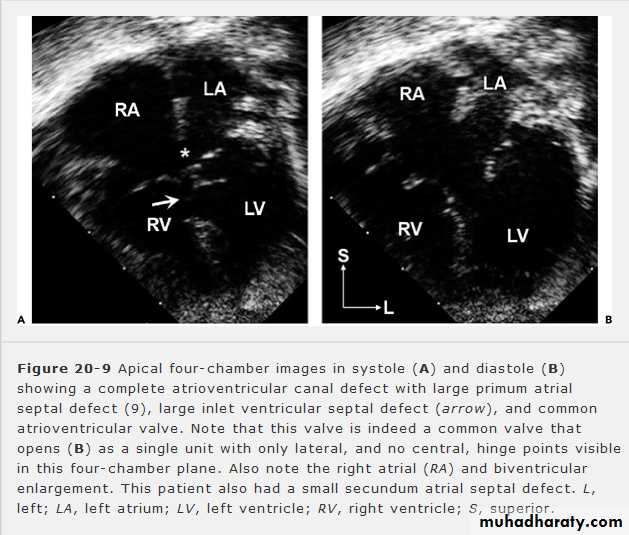

ATRIOVANTRICULAR SEPTAL DEFECT (cont.):

• Echo: is diagnostic.A4C view in systole(A) & diastole (B) showing complete AV septal defect.